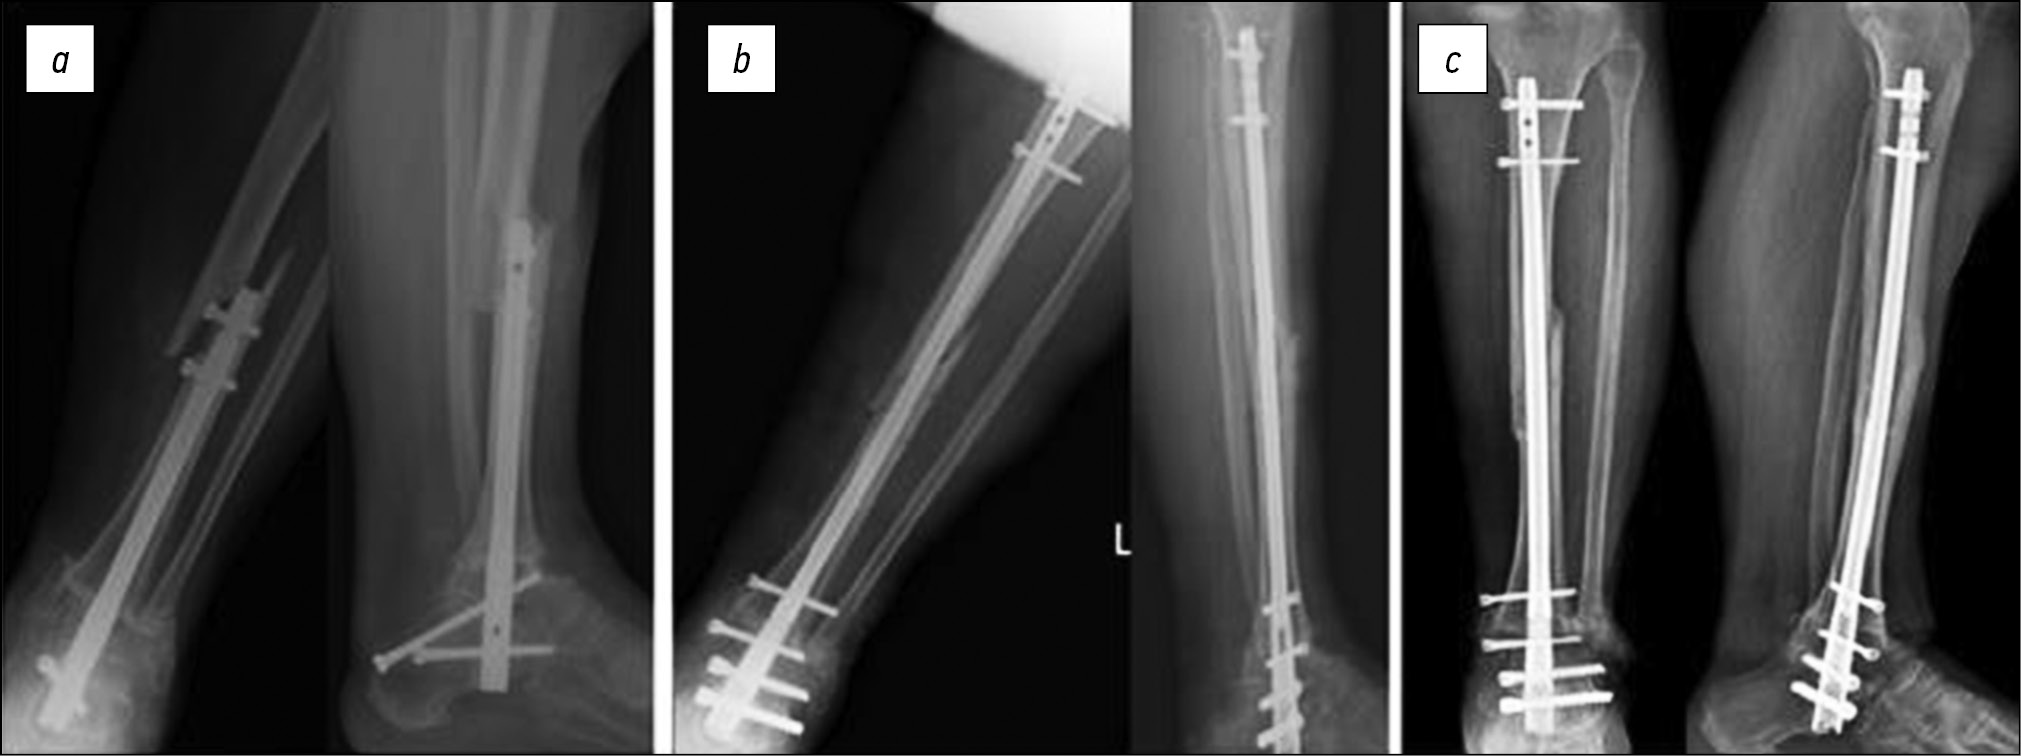

Больной Я., 64 года, госпитализирован для выполнения ревизионного оперативного вмешательства через 4 месяца после осуществления первичной операции с жалобами на боли, появившиеся после «щелчка» при нагрузке на конечность. При обследовании установлены нестабильность фиксации голеностопного сустава в результате разрушения металлоконструкции, удовлетворительное состояние костных структур, парциальное формирование костного анкилоза в зоне голеностопного сустава. С учётом этого выполнили удаление ранее установленной металлоконструкции, продольную остеотомию таранной и большеберцовой кости по линии формирующегося анкилоза, реостеосинтез интрамедуллярным стержнем с перекрытием зоны ранее установленных блокирующих винтов с целью профилактики периимплантного перелома большеберцовой кости (рис. 2).

Рис. 2. Рентгенограммы больного Я.: a — через 4 месяца после первичного оперативного вмешательства, b — после ревизионного оперативного вмешательства, c — через 6 месяцев после ревизионного оперативного вмешательства

Fig. 2. Radiographs of patient Ya.: a — 4 months after his first surgery, b — the revision surgery, and c — 6 months after the revision surgery